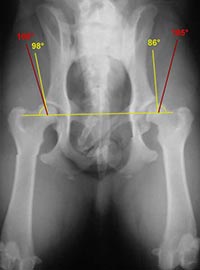

Norberg WinkelEin wesentliches Kriterium für die Auswertung ist der Norberg-Winkel. Er ist als der Winkel definiert, der zwischen dem Zentrum des Oberschenkel-kopfes und dem vorderen Pfannenrand abgetragen wird. Bei einem HD-freien Tier sollte er mehr als 105° betragen (rote Linien).